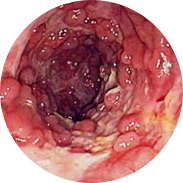

Causas de la aparición de hemorroides

• Genética

Resultó que el 85% de los parientes consanguíneos también tenían síntomas de hemorroides

• Estilo de vida sedentario

Esto se aplica principalmente a los conductores y trabajadores de oficina

• Embarazo

El útero agrandado presiona los vasos del ano, lo que hace que surjan ganglios hemorroidales externos

• Género

Las mujeres tienen hemorroides por un estilo de vida sedentario y saltos hormonales, y los hombres por cargas excesivas y levantamiento de pesas

• Factor mecánico

Lesiones, quemaduras y otros efectos mecánicos en el recto y el ano